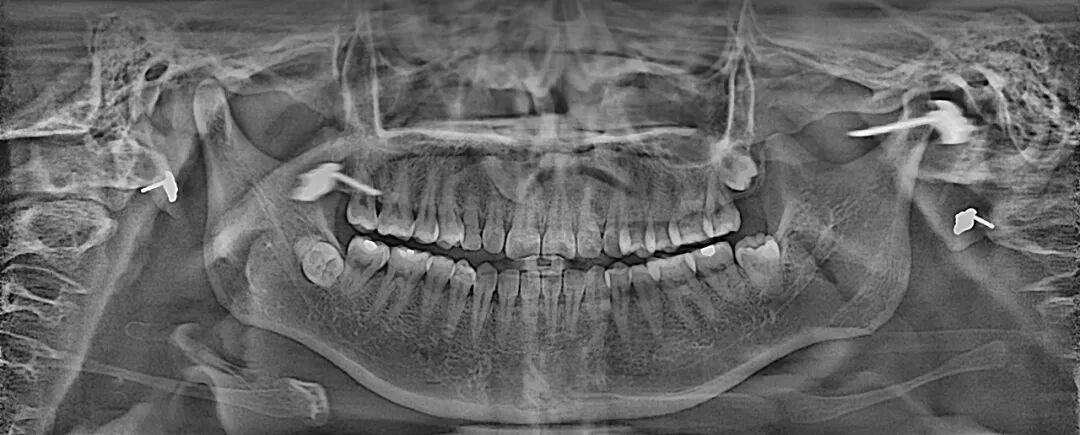

“伯爵Bondream”智能3D全景由外向內(nèi)33張全景片觀查

普通全景圖(同一患者前牙區(qū)埋伏牙觀察)